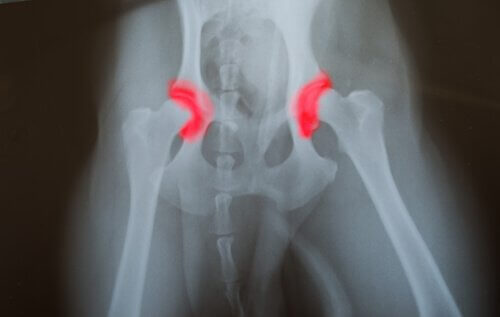

Lonkan tai kyynärpään dysplasia on perinnöllinen sairaus, eli se periytyy sukupolvelta seuraavalle. Sitä ilmenee luissa, jotka muodostavat nivelen – olipa tässä kyseessä lonkka tai kyynärpää -, ja nämä eivät ole oikeassa paikassa tai linjassa. Siten ne hierovat toisiaan vasten ja tekevät liikkumisesta epänormaalia.

Tämä sitten aiheuttaa luiden kulumisen nopeutumista, mikä johtaa puolestaan nivelten toiminnan ongelmiin ja muihin haittoihin. Yksi tämän sairauden vaikeimmista puolista on se, että se etenee usein oireettomasti, eli sitä on vaikea huomata lemmikillä.